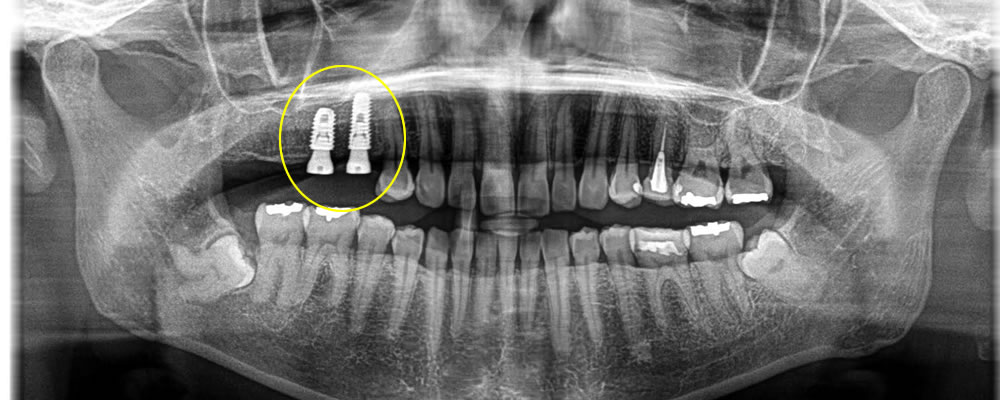

インプラント治療完了後のレントゲン・口腔内写真

3ヵ月待機期間を設け、インプラント体と骨がしっかり結合している事を確認した後、上部のジルコニアの歯を作成し、装着しました。

噛み合わせの回復はもちろん、審美的にも綺麗な歯をいれる事ができ、患者さまに満足して頂けました。